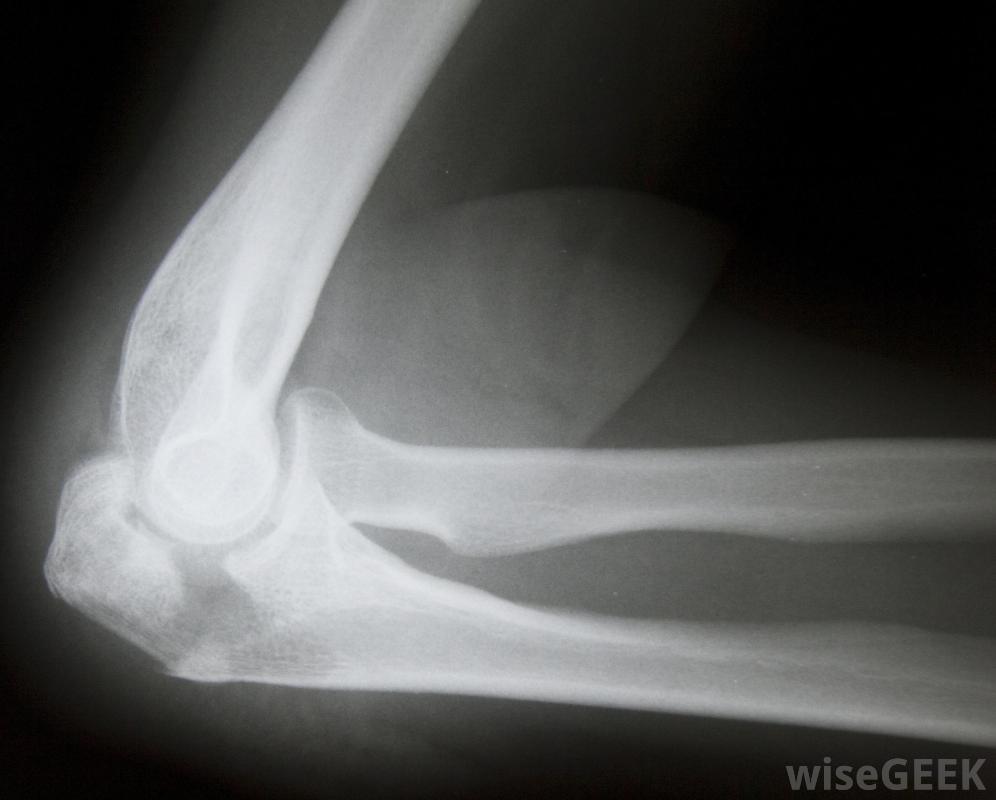

X光有助于确定尺骨鹰嘴骨折的确切位置和严重程度。尺骨鹰嘴本身是一块坚固的骨头,但由于它靠近身体,它仍然很容易骨折骨骼没有被周围组织很好的保护,在活跃的人群中是一个非常常见的创伤部位。尺骨骨折可能是由于钝器的直接撞击、大部分冲击力被肘部吸收的坠落、或是关节脱臼的笨拙弯曲或扭转运动造成的老年人也有患尺骨鹰嘴骨折的风险,因为他们的骨头通常比较脆弱,而且更容易摔倒尺骨鹰嘴骨折会立即引起肘部疼痛尺骨鹰嘴骨折通常会导致突然疼痛,很快就会伴有头晕和恶心。肘关节肿胀,手臂无法移动。在肘部受伤的情况下,用吊索固定关节非常重要,直到可以寻求专业医疗护理应立即送至急诊室接受正确诊断和止痛药物。

参加接触性运动(如摔跤)的人可能发生尺骨鹰嘴骨折进入急诊室后,医生通常会口服或注射药物来缓解疼痛和肿胀的症状。医生可以对肘部进行x光和磁共振成像扫描,以确定确切的情况骨折的位置和严重程度。大多数尺骨鹰嘴骨折不会对骨骼或周围结构造成严重损害。患者只需戴上吊索或支架数周,并定期接受医生检查,以确保骨骼正确愈合。吊带可在两个月内取下,此时患者可能需要进行锻炼或参加物理治疗以恢复体力。